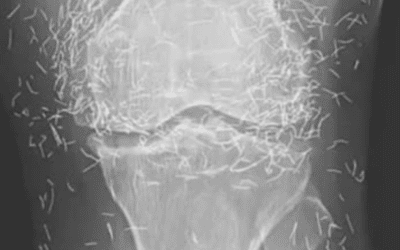

Röntgenaufnahme enthüllt Hunderte von Goldnadeln in den Knien einer Frau

Röntgenaufnahme enthüllt Hunderte von Goldnadeln in den Knien einer Frau Als Ärzte ein Röntgenbild der Knie einer alten Frau untersuchten,…